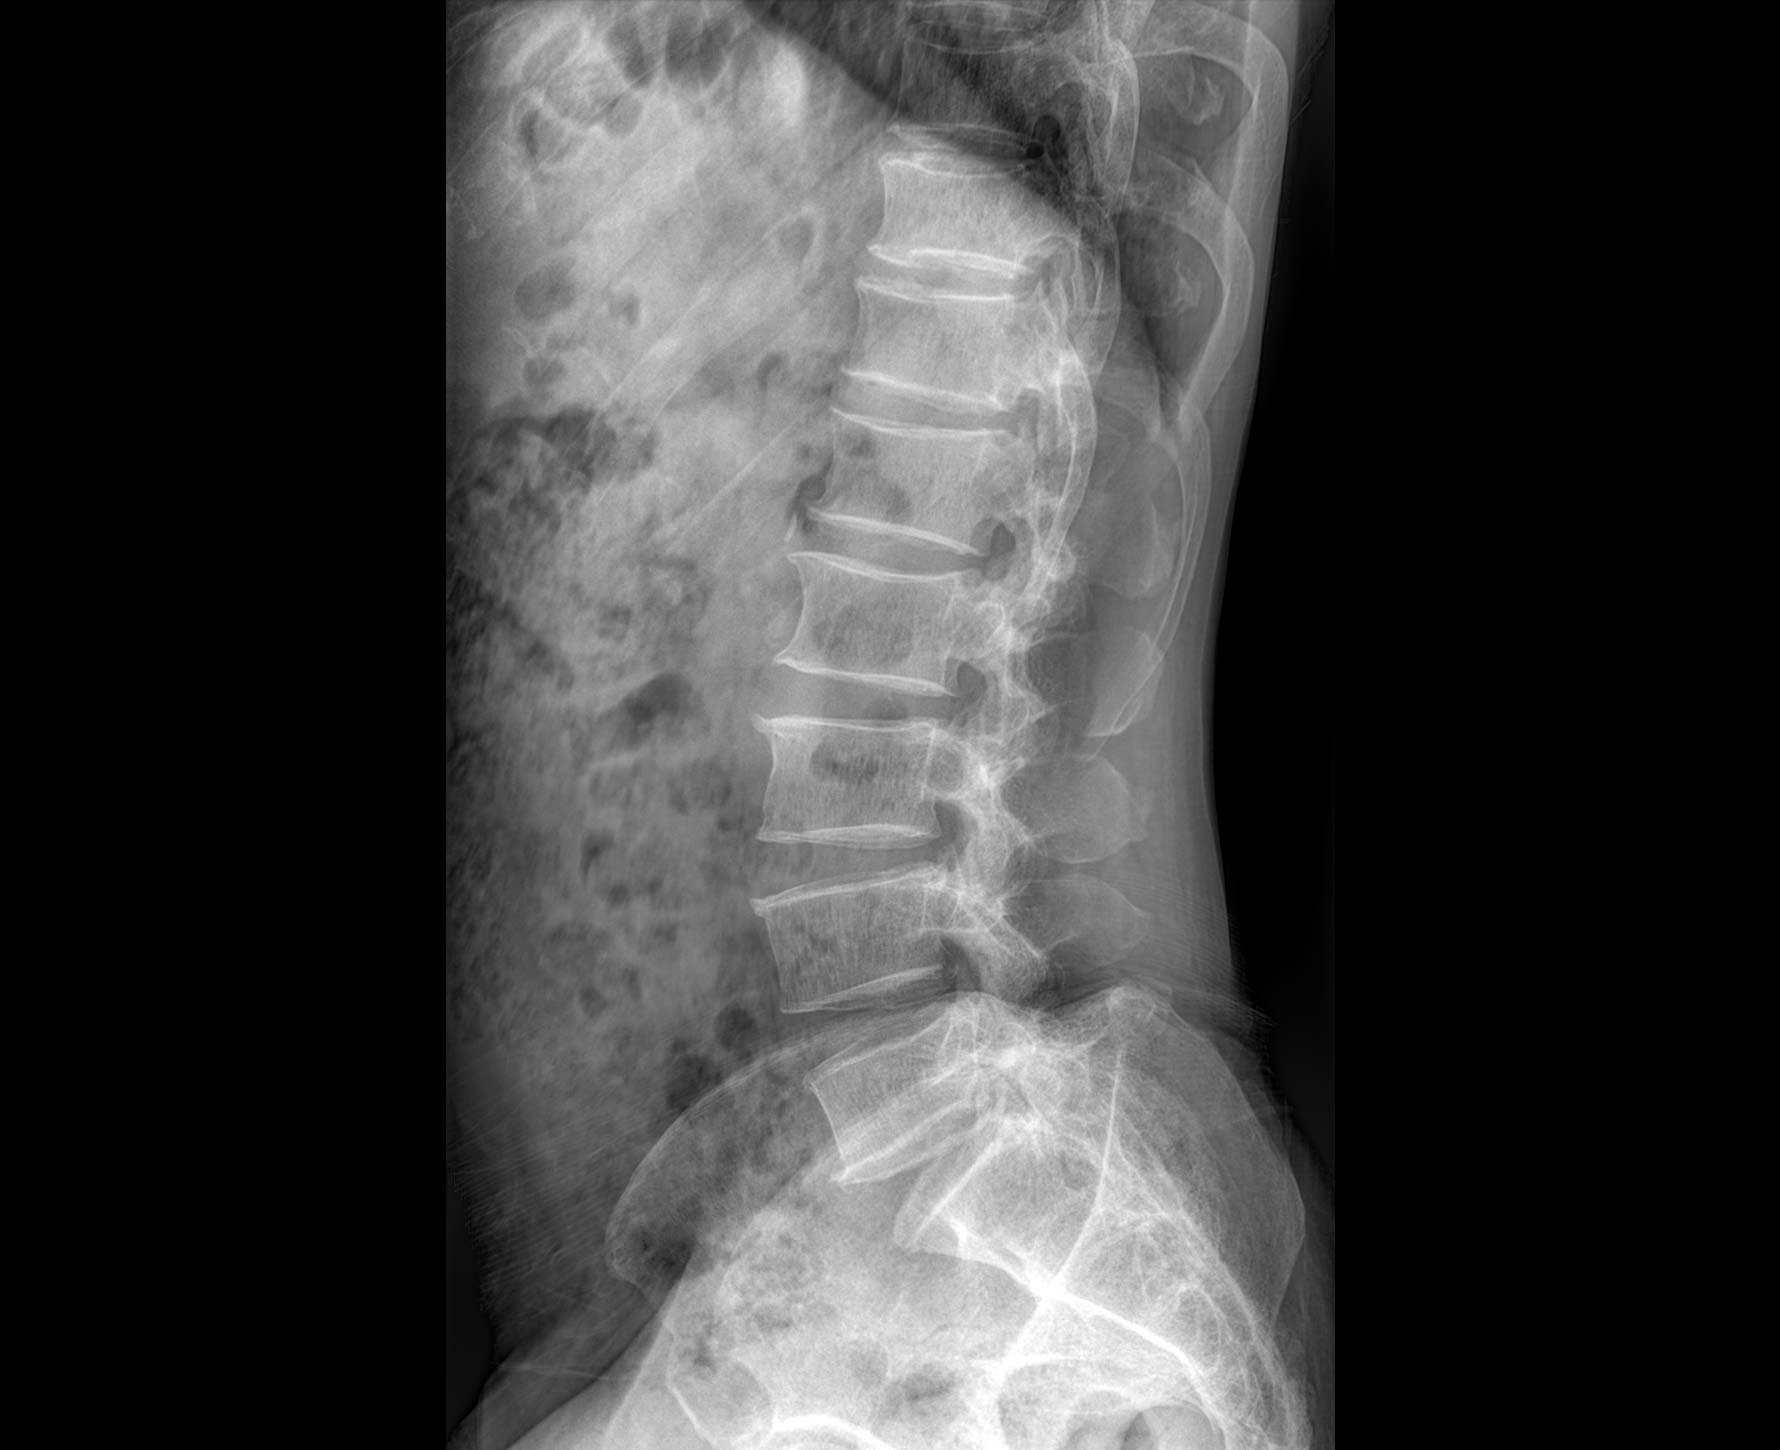

• 透视

适用于全身各

部位透视检查

临床图像